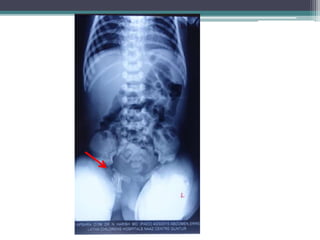

Vertebral Coronal Clefts

•Failure of fusion of

anterior and posterior

ossification centers

•Best seen on lateral

Xray films

•Radiolucent band

running through the

vertebral bodies